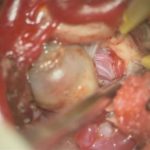

'19年5月

30代

富永/久貝

右中小脳脚 出血再発

SM 3(S1,E1,V1)

米国の病院

No.359 モニタリング

No.359 手術前

No.359 手術中

No.359 手術後

出血既往があり。2回の手術前血管内手術の後に、

Lateral transpeduncular approachにより再々出血予防を目的に

摘出手術を行う。完全摘出であることを確認した。

手術による合併症や後遺症なしで退院した。経過良好。